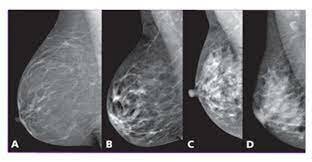

Frederick Hicken presenta un nuevo método de diagnóstico al que nombra mamografía y se basó en la aplicación de medios de contraste por los conductos galactóforos.